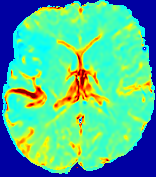

Slice #1Slice #2Slice #3Slice #4Slice #5Slice #6Dgtsuperscript𝐷gtD^{\text{gt}}Refer to captionRefer to captionRefer to captionRefer to captionRefer to captionRefer to captionDestsuperscript𝐷estD^{\text{est}}Refer to captionRefer to captionRefer to captionRefer to captionRefer to captionRefer to captionRefer to caption0.300.300.300.240.240.240.180.180.180.120.120.120.060.060.060.000.000.00(mm2/s)𝑚superscript𝑚2𝑠(mm^{2}/s)𝐕est𝟐subscriptnormsuperscript𝐕est2\|\bf{V}^{\text{est}}\|_{2}Refer to captionRefer to captionRefer to captionRefer to captionRefer to captionRefer to captionRefer to caption0.00300.00300.00300.00240.00240.00240.00180.00180.00180.00120.00120.00120.00060.00060.00060.00000.00000.0000(mm/s)𝑚𝑚𝑠(mm/s)

Figure 15: PIANO identifiability testing: diffusion imaging via advection-diffusion. Top row shows Dgtsuperscript𝐷gtD^{\text{gt}} used for simulating ground truth pure diffusion. Rows below show the estimated Destsuperscript𝐷estD^{\text{est}} and 𝐕est2subscriptnormsuperscript𝐕est2\|{\bf{V}}^{\text{est}}\|_{2} on corresponding slices. Note that the plotted value scale for 𝐕est2subscriptnormsuperscript𝐕est2\|{\bf{V}}^{\text{est}}\|_{2} is 0.01 of that for Dgtsuperscript𝐷gtD^{\text{gt}} and Destsuperscript𝐷estD^{\text{est}}.

Similarly, we test the behavior of PIANO when estimating both advection and diffusion from a pure diffusion-driven process. The goal is to determine if PIANO is able to recognize that there is only diffusion governing the given concentration time-series. We use the same ‘Diffusion Imaging’ data simulation of Sec. 4.2.1 as the concentration dataset, PIANO estimates both velocity 𝐕estsuperscript𝐕est{\bf{V}}^{\text{est}} and diffusivity Destsuperscript𝐷estD^{\text{est}}. Estimation results in Fig. 15 confirm PIANO’s identifiability again: the estimated 𝐕est2subscriptnormsuperscript𝐕est2\|{\bf{V}}^{\text{est}}\|_{2} is almost invisible compared to Destsuperscript𝐷estD^{\text{est}}, even plotted with a 1%percent11\% value range compared to that for Destsuperscript𝐷estD^{\text{est}}. On the other hand, Destsuperscript𝐷estD^{\text{est}} achieves comparable estimation performance as ‘Diffusion Imaging via Diffusion’ in which PIANO predicts Destsuperscript𝐷estD^{\text{est}} alone (shown in Fig. 13).